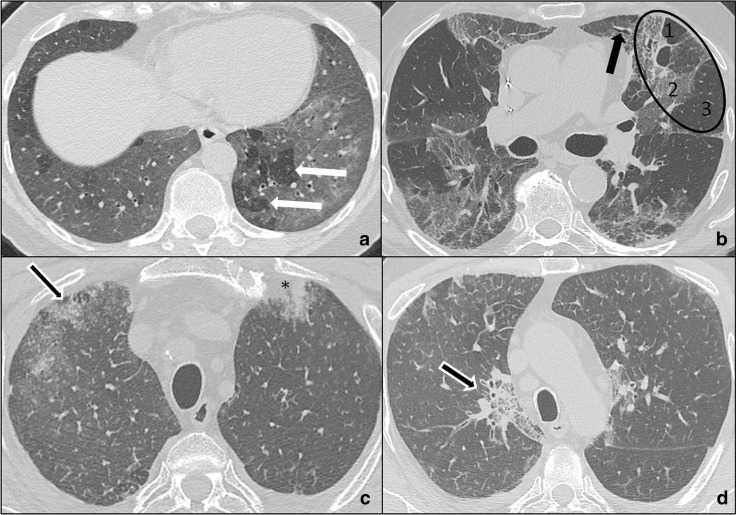

Fig. 4.

a–d COVID-19 pneumonia differential diagnoses: hypersensitivity pneumonia and eosinophilic pneumonia. HRTCs of a patient affected by hypersensitivity pneumonia at baseline (a) and after two years (b): acute/subacute hypersensitivity pneumonia is characterised by diffuse ground-glass opacities clearly demarcated from air trapping areas (white arrows in a); chronic hypersensitivity pneumonia presents with architectural distortions and traction bronchiectases (black arrow in b). The triad of mosaic oligemia (1 in b), ground-glass opacities (2 in b) and normal pulmonary parenchyma (3 in b) is defined as “headcheese sign” (black oval in b). HRTC of acute eosinophilic pneumonia (c, d) showing confluent crazy paving opacities (white bordered black arrows in c, d) coexisting with consolidations (black asterisk in c) and slight bilateral pleural effusions